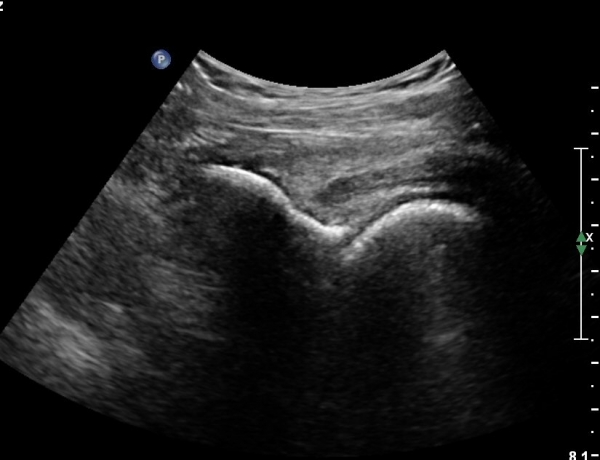

ÃÊÀ½ÆÄ °Ë»ç